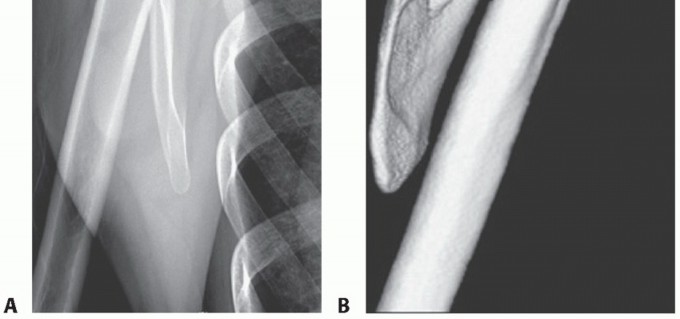

The patient is positioned in the prone position for both arthroscopic and open techniques (FIG 5).

The involved arm is placed in internal rotation against the patient's lower back (chicken wing position). This will cause the scapula to wing out from the thorax and make the superomedial angle more prominent.

FIG 5 • The operating room setup for arthroscopic scapulothoracic bursectomy. The patient is positioned prone with the hand of the involved shoulder placed behind the back in order to lift the scapula off the chest wall.*

FIG 5 • The operating room setup for arthroscopic scapulothoracic bursectomy. The patient is positioned prone with the hand of the involved shoulder placed behind the back in order to lift the scapula off the chest wall.*